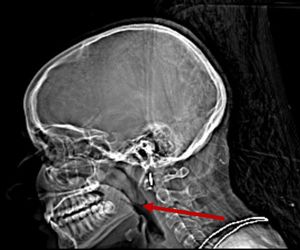

A 22-year-old female with a history of right sided nasal obstruction, cheek pain and new onset of snoring. Patient was initially treated conservatively with oral antibiotics, and symptomatic medical management, but had minimal improvement and eventually progression of symptoms.